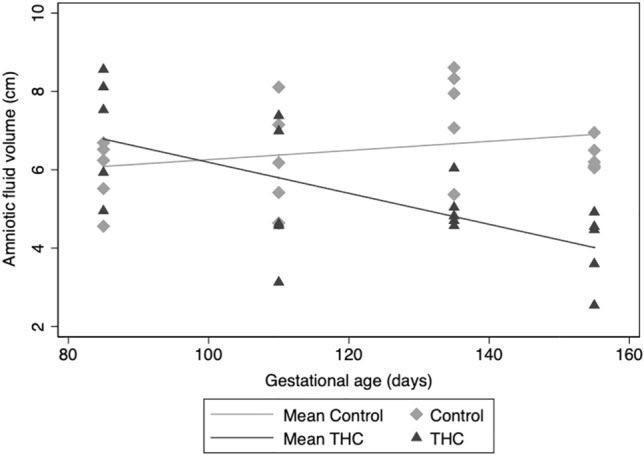

Amniotic fluid volume

An expected increase in amniotic fluid volume across pregnancy was observed in control animals (Fig. 2), but a statistically significant decrease in amniotic fluid volume throughout pregnancy was present in THC-exposed animals (p < 0.001).